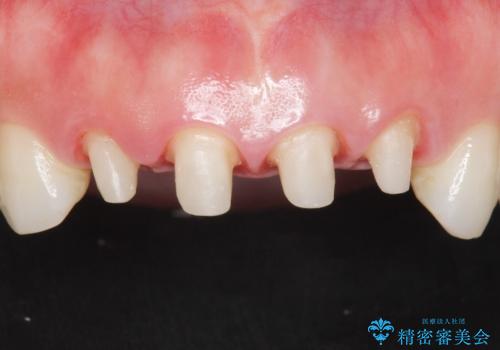

- 10年前に美容外科クリニックで前歯を治療したところ、あまりに不自然で逆にコンプレックスになってしまったことを主訴に来院された患者様です。

前歯4本の被せものは連結されており、不自然なだけではなく清掃性も悪く歯茎が著しく腫脹していました。

レントゲンを撮影したところ土台の植立も不十分であったため、土台からやりかえることにしました。

歯茎の腫脹が顕著であったため、適合の良いオーダーメイドの仮歯に変え、歯茎の状態が良くなるまで1ヶ月待ったのち型取りを行いました。